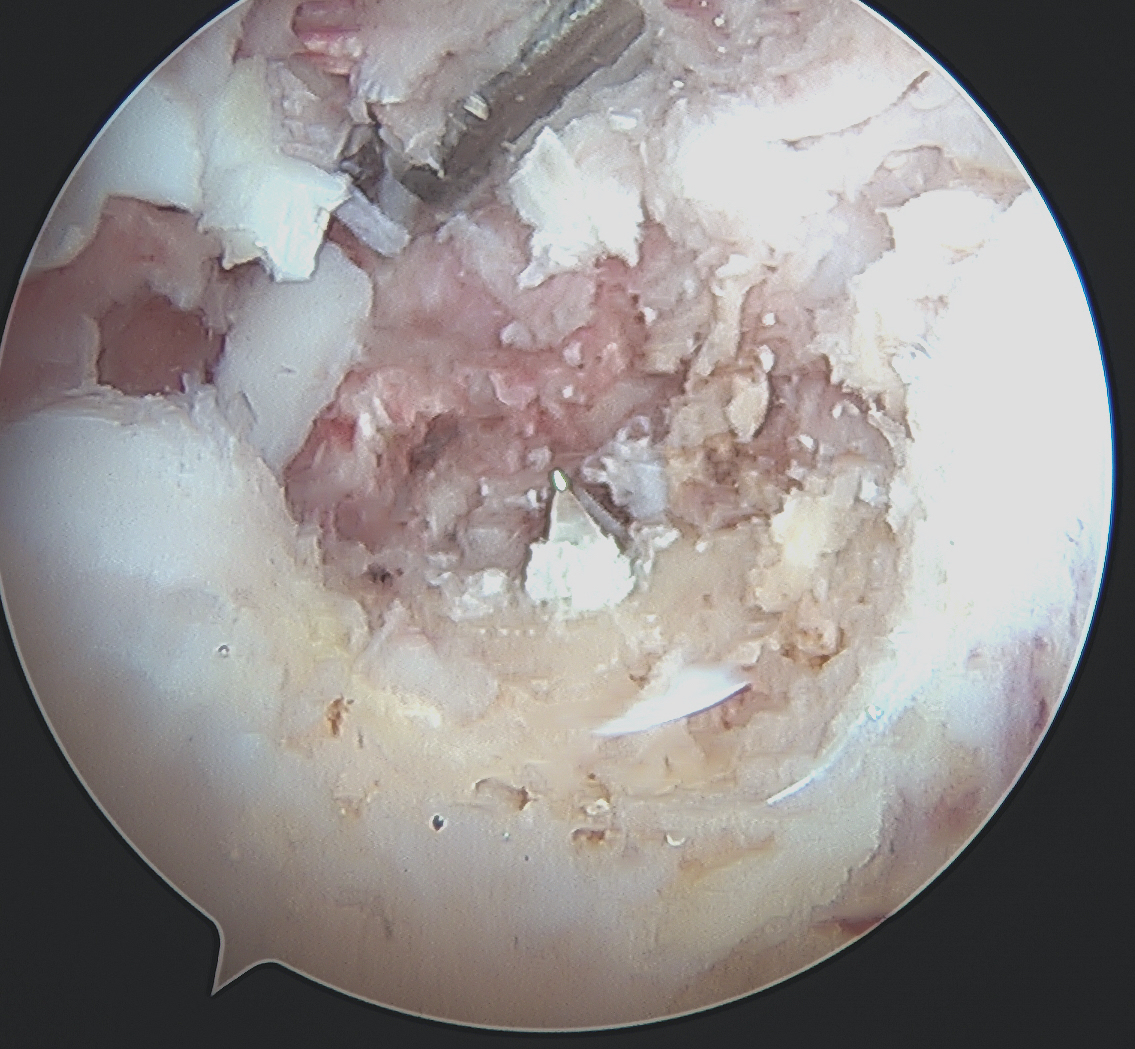

PCL Tibial Tunnel

Change to 70o scope

- under vision clear PCL facet

- release posterior capsule from bone (visualise popliteus muscle)

- release posterior speptum (attaches to PCL, and divides knee into posteromedial and posterolateral)

- PCL guide 65o angle

- tibial guide placed just lateral to crest to ensure room for more medial ACL tunnel

- place on posterior facet, slightly lateral

- check on fluoroscopy on PCL facet

- protect guide wire with curette or switching stick via PM cannula

- carefully ream 10 mm tunnel

- clear tunnel entrance of debris